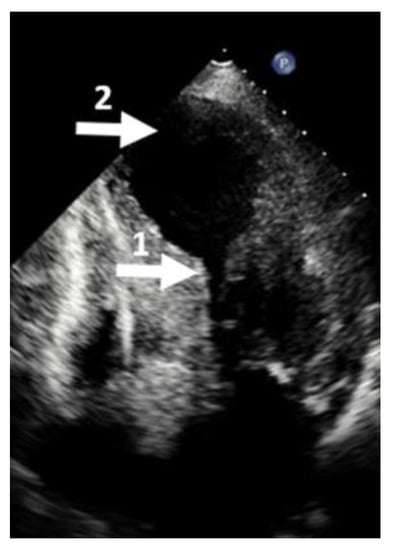

2. Mechanism of LV Aneurysm Formation in HCM

3. Diagnosis of LV Aneurysm in HCM